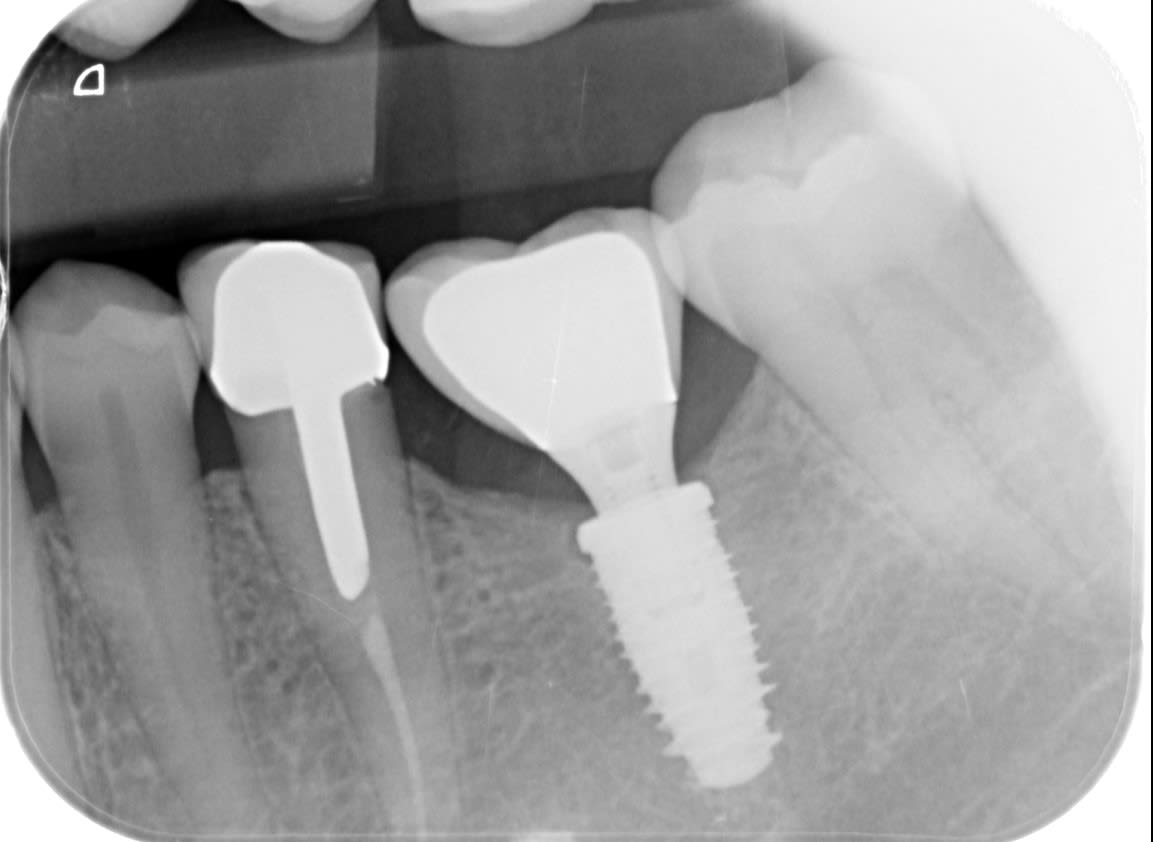

Bonjour, quel implant pour ce pilier ? merci par avance.

Pour le pilier avec sa couronne….heureusement caractéristique….c’est du 3i

Pour l’implant en radio, oui biotech kontact (s ou pas, on s’en moque c’est la même connexion)